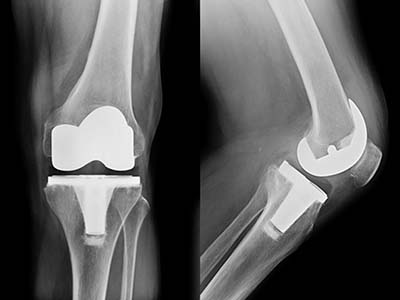

Knee Replacement

Total Knee Replacement (TKR) A Complete Guide Knee replacement surgery, also known as knee arthroplasty,…